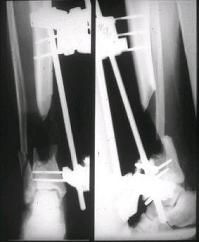

При отсутствии альтернативы закрытия дефекта специалистом, тогда кожным лоскутом на широком основании "cross leg flap". Рекомендую подготовку донорского участока заранее, на задней поверхности голени, срез кожи с подкожной клетчаткой, как на вашем рисунке, приподнимается лоскут от фасции, после гемостаза кожа зашивается заново.

Таким образом подготовленный участок хорошо приживается засчет образования краевого кровообращения, особенно у пожилых и у больных с заболеваниями периферических сосудов. Через 10-12 дней лоскут повторно выделяется по заживающей линии и закрывается дефект, а на донорский участок кожная пластика.

здесь случай с политравмой, перелом зафиксирован наружным фиксатором, после третьей irrigation&debridment фиксация бедра пластиной с последующей кожной пластикой.